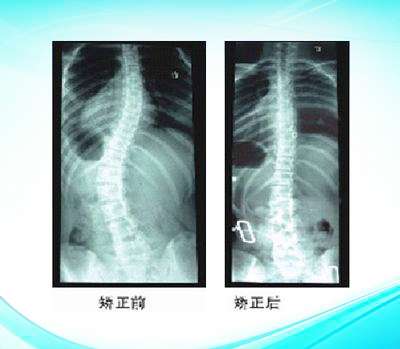

脊柱側(cè)彎矯形產(chǎn)品

色努脊柱側(cè)彎矯形器6

色努脊柱側(cè)彎矯形器

脊柱側(cè)彎矯形器3

脊柱側(cè)彎矯形器2

脊柱側(cè)彎矯形器